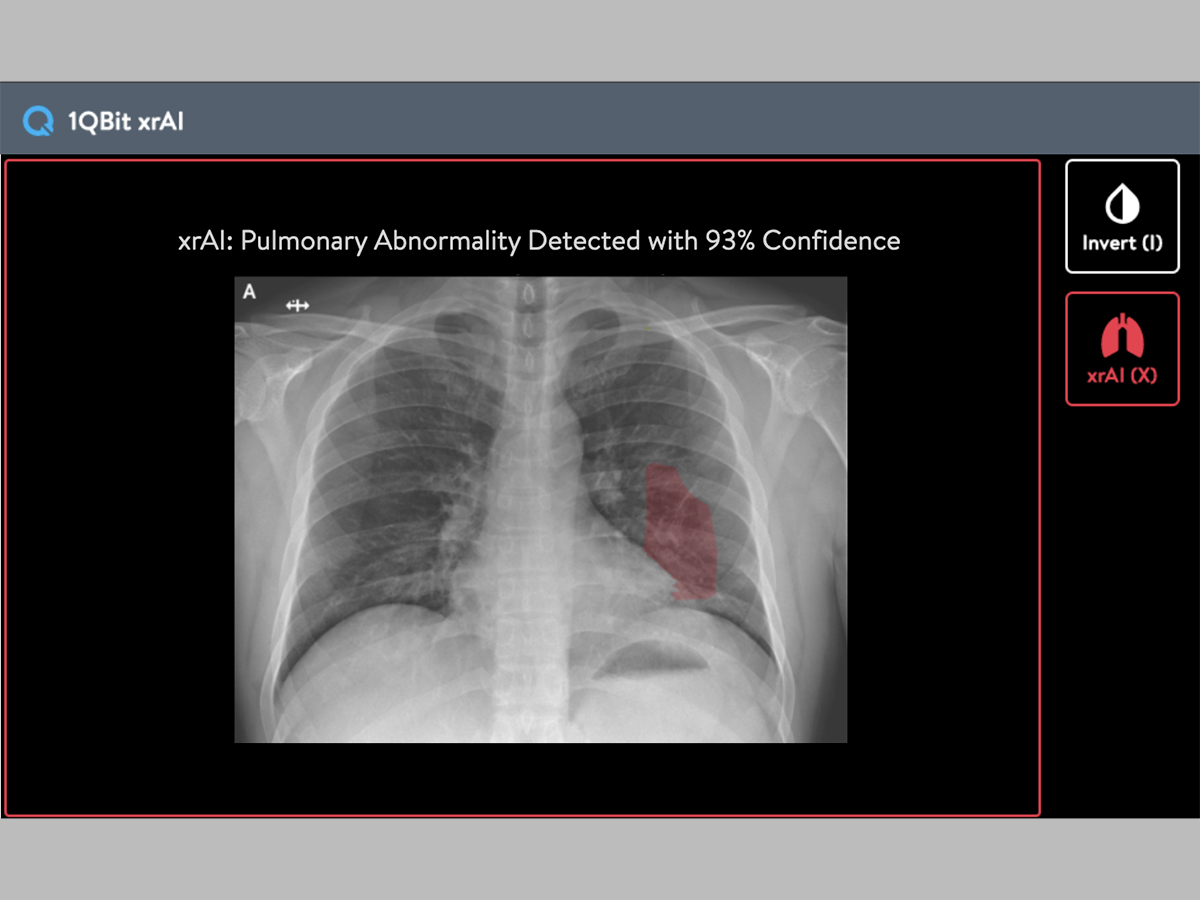

Health Canada Accelerates Approval Of Ai Driven Covid 19 Tool 2020 04 30 Bioworld

Collaboration Aims To Fast Track Ai Solution For Rapid Covid 19 Diagnosis Using Chest X Rays